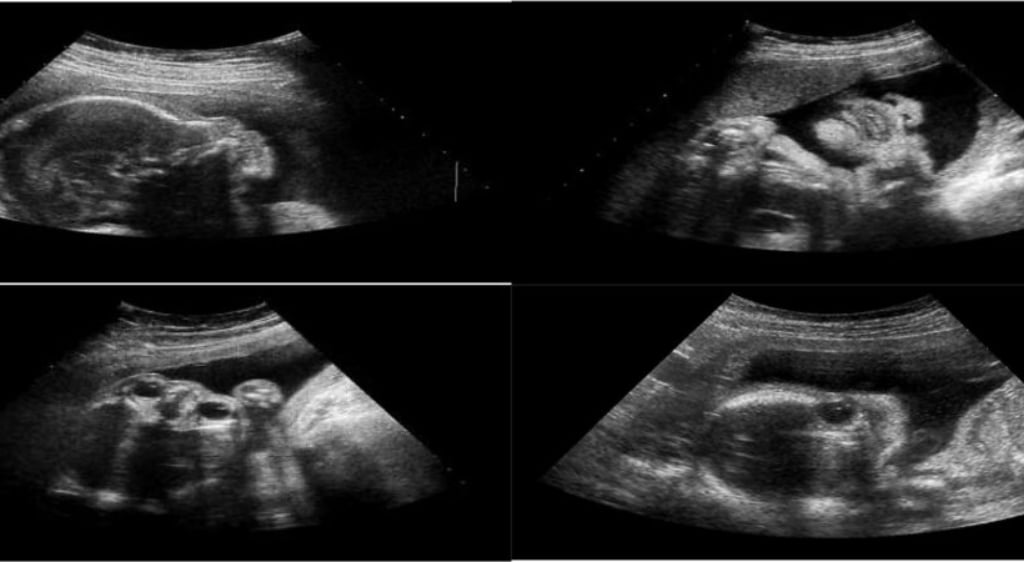

Siêu âm 3D, 4D

Khác với siêu âm truyền thống, với công nghệ 3D, 4D cho phép cung cấp những hình ảnh thấy chiều cao, chiều rộng, chiều sâu của thai nhi và cơ quan sinh sản. Cách thực hiện tương tự như siêu âm tiêu chuẩn, nhưng thiết bị kiểm tra sử dụng đầu dò và thiết bị đặc biệt để tạo ra hình ảnh 3D, đặc biệt với công nghệ 4D, hình ảnh rõ hơn về khuôn mặt và chuyển động của bé.

Mốc 2: Thai kỳ từ 22-23 tuần

Thời gian giữa thai kỳ (thai nhi từ 22-23 tuần) cung cấp cho mẹ bầu những thông tin về:

- Kiểm tra nhịp tim, vị trí và những chuyển động của trẻ

- Kiểm tra vị trí nhau thai

- Xác định kích thước tử cung của mẹ bầu

- Xác định những bất thường về thể chất của trẻ

- Xác định giới tính của bé.

Mốc 3: Thai kỳ từ 31-32 tuần

Trong lần khám cuối cùng trước khi sinh, kết quả xét nghiệm đưa ra thông tin về:

- Kiểm tra sự tăng trưởng, sức khỏe của bé

- Kiểm tra tổng quát về nhau thai, nước ối của mẹ

- Tìm hiểu về tình trạng sinh mổ hay không (tùy vào tình trạng của trẻ)

- Kiểm tra những dấu hiệu bất thường như chảy máu âm đạo,…